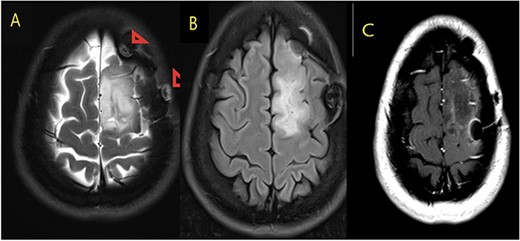

Our patient is a 31-year-old female who presented to the emergency department due to two episodes of generalized tonic colonic seizures. Upon presentation, the patient was administered with supplemental oxygen. She was drowsy and confused while exhibiting signs of right-sided hemiparesis and paralysis. Her pupils were 3 mm and reacted briskly while she showed good left-sided localizing. Her seizures terminated after intravenous administration of midazolam at 5 mg. Further, it was known that she has been symptomatic for 1 month and had been suffering from episodes of seizures, with shaking and tremors of upper limbs, and brief episodes of blackouts for about a minute. These episodes were associated with headache and nausea but were self-limited. Seizures recurred two to three times per week. She denied any fall, tongue bite, loss of consciousness, and limb weakness or numbness. A computerized tomography (CT) scan was suggested, which showed left high parietal hypodensity with vasogenic edema (Fig. 1). She was recommended Keppra 1.5 g and dexamethasone 12 mg. Further, a contrast MRI of the brain was performed (Fig. 2). After a thorough evaluation of the patient’s medical records and current condition, it was decided to proceed with an excision of the tumor using the AC technique. To foster trust and comfort, the same anesthesia and surgical teams were assigned to the patient. Before the procedure, the patient was fully informed about the nature of the procedure and the possibility of a failed outcome or further need for a conversion to general anesthesia. To assess the patient’s cognitive and language abilities, preagreed questions and exercises were performed. These included memory-related queries, such as asking for the patient’s phone number and the names of her dog, and motor commands, such as squeezing a squeaky toy. The patient was prepared for awake navigator-assisted left frontal craniotomy for excision of the left frontal lobe space-occupying lesion, which was suspected to be either a low-grade glioma or fibrous dysplasia. During the surgical procedure, a central line was placed in the right jugular vein using ultrasound, followed by the insertion of a right radial arterial line, a urinary catheter, and two additional venous lines. The patient received a continuous flow of 4–6 l of oxygen per minute. To achieve conscious sedation, the patient received infusions of remifentanil and propofol at varying rates. The patient underwent a 5-hour surgical procedure to remove a tumor. During the procedure, the patient was under sedation and was regularly tested for response to predetermined commands. Her conscious sedation level fluctuated, but she never lost consciousness. The removal of the tumor was successful, and postoperative examination revealed normal motor function and cranial nerve function. The patient was taken to the intensive care unit, and postoperative MRI showed a reduction in the size of the mass lesion in the left frontal lobe/superior frontal gyrus along with mild vasogenic edema surrounding it (Fig. 3).

MRI brain with contrast; (A) T2, (B) T1, and (C) T1 post contrast; space occupying cortical mass lesion in the left frontal lobe/superior frontal gyrus showing mild faint minimal contrast enhancement (C) (low-grade glioma).